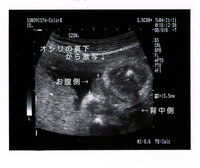

Jul 16, 14 · こんにちは。 今妊娠19週目の妊婦です。 12週の経膣エコーで股の方に女の子の象徴であるコーヒー豆のような形をした部分を発見しました。写真にも残っています。 しかしそのときは先生にはまったく何も言われませんでした。次のエコーの時には、女の子の判定判断ともされる、いわゆる「コーヒー豆」が見えても 中々確定が頂けません。 そして妊娠8ヶ月頃にようやく あ~、やっと分かった〜!と、スッキリした気持ちでいっぱいでした。残念ながら我が家に女の子はいないので、とてもわかりやすい画像をゼクシィbabyよりお借りしました。 女の子の場合、 会陰部に"木の葉マーク"や"コーヒー豆"のような真ん中に何かしらの線が入っていることで判断 されます。

男の子はピーナツ状の突起物、女の子は木の葉やコーヒー豆が股間に見えますが、ときには判定間違いも起こります。 消化管のエコー (超音波)検査のテキスト bechi 消化管エコーのスキルアップに!女の子 エコー コーヒー豆 画像 女の子 エコー コーヒー豆 画像 のランキングをご紹介。エコー タマタマ 木の葉 , 陰嚢や睾丸(タマタマ)がみえる 大きく成長してくると、 陰嚢やその中にある睾丸(精巣)がエコーに映る ことがあります。 陰嚢だけをみると、女の子の特徴とされている木の葉型やコーヒー豆と見紛うことがありますが、その中に白い円形のものが写っていれば

女の子のエコー写真の特徴2:三本線 女の子のエコー写真の特徴2つめは、三本線です。女の子の場合は、股の割れ目と大陰唇で見分けることができます。 この割れ目が女の子の外性器です。 三本線やコーヒー豆などと表現されることもあります。